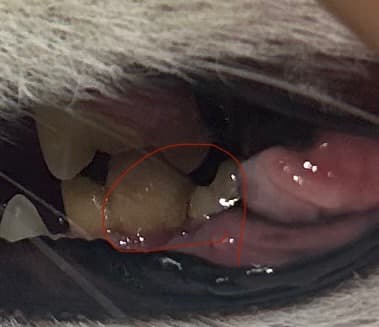

좌측 하악 어금니 파절로 병원갔더니

우측 하악 어금니도 깨져있다고 하네요

좌측은 이미 뿌리만있어서 발치확정이고

우측은 깨져있지만 턱이 떨리지도 않고 잘 씹고있는 상태인데 동네병원에선 양측 발치를 권하더라구요

말씀해주신 상황을 정리하면, 좌측 하악 어금니는 치관이 다 깨지고 뿌리만 남은 상태라 발치가 꼭 필요합니다. 반면 우측 하악 어금니는 파절은 있지만 겉보기에 잘 씹고 있고 턱도 떨지 않아 보호자님께서 바로 발치를 해야 하나 고민하시는 상황입니다.

치아가 깨졌을 때 중요한 기준은 치아 속 신경(치수)이 드러났는지 여부입니다.

1. 신경이 드러난 경우에는 시간이 지나면서 통증이 생기고, 결국 뿌리 끝에 염증이나 고름주머니가 생길 수 있습니다. 지금은 괜찮아 보여도, 나중에 심한 통증이나 턱뼈 문제로 이어질 수 있기 때문에 결국 발치가 필요합니다.

2. 신경이 드러나지 않은 경우라면 당장 발치를 하지 않고 지켜볼 수도 있습니다. 다만 이 경우에도 시간이 지나면서 금이 더 가거나 염증으로 진행될 가능성이 있어, 정기적으로 상태를 확인해 주는 것이 필요합니다.

문제는 동물들이 치통을 잘 표현하지 않고, 보호자님 보시기엔 밥을 잘 먹어도 속으로는 불편할 수 있다는 점입니다. 그래서 단순히 겉모습만 보고 판단하기보다는, 치과 방사선으로 뿌리 끝 염증이 있는지, 신경이 노출되었는지를 확인하는 것이 가장 확실합니다.

정리하면, 좌측은 발치가 확정이고, 우측은 “무조건 발치”라기보다는 방사선 검사와 신경 노출 여부 확인 후 결정하는 것이 합리적입니다. 다만 추후 문제가 생길 가능성을 완전히 배제할 수는 없기에, 많은 경우 예방 차원에서 발치를 권하기도 합니다.

즉, 아이가 지금 아프지 않아 보여도 치아 파절은 나중에 큰 문제로 이어질 수 있으니, 방사선 검사를 통해 정확히 확인하고 결정하시길 권장드립니다.